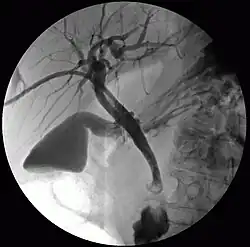

Die perkutane transhepatische Cholangiographie (PTC) ist ein interventionelles Verfahren, bei dem mit Hilfe einer dünnen Hohlnadel unter Durchleuchtungskontrolle perkutan (durch die Haut) durch Punktion der Leber Röntgenkontrastmittel in das Gallenwegsystem eingebracht wird.

Bei der PTC handelt es sich um eine direkte Cholangiographie, bei der eine Darstellung der Gallenwege inner- und außerhalb der Leber möglich ist. Wichtig zu wissen ist dabei, dass sich die beiden (den größeren rechten und den kleineren linken) Leberlappen drainierenden Hauptgallengänge in der sog. Hepatikusgabelung vereinigen und die Galle aus der Leber über den gemeinsamen Gallengang (den Ductus hepatocholedochus) ins Duodenum ableiten. Die Darstellung der Gallengänge in der PTC und ERCP stellt im Vergleich zur MRT/MRCP und dem CT weiterhin den Goldstandard dar.